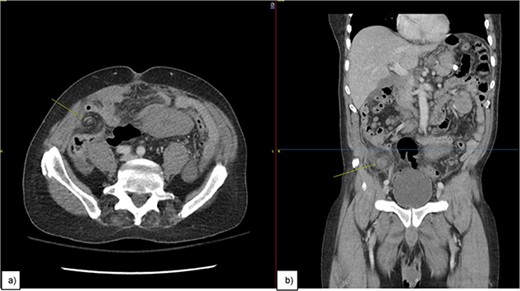

A 72-year-old male, who had previously been diagnosed with MCL in 2021 and had undergone R-CHOP therapy achieving remission, presented to the Emergency Department with a history of right lower quadrant abdominal pain, lightheadedness, and persistent nausea for over a week. Upon initial evaluation, computed tomography (CT) (Fig. 1) raised the suspicion of a potential volvulus. However, upon transfer to the operating room, a markedly distended appendix, accompanied by substantial lymphadenopathy affecting the mesoappendix, was unveiled (Figs 3–5). An appendectomy was subsequently performed, and the excised specimen was promptly dispatched for pathological examination, which confirmed the presence of MCL.

An image of the mass (pointing arrow) on (a) axial view showing Swerling sign, (b) coronal view.

MCL often starts with lymph node enlargement and can spread to the bone marrow, liver, and gastrointestinal tract, especially the colon. It rarely affects the appendix, typically through nearby ileocecal involvement [4, 5]. In our case, a 1.4 cm appendiceal mass was found on a positron emission tomography CT (PET-CT) scan a year prior to presenting with the symptoms, but follow-up was not pursued until the patient presented with pain and obstructive symptoms due to an enlarged appendix, confirmed by CT to be a “swirl sign” indicative of volvulus (Figs 1 and 2). The appendix measured 5 cm in width and 16.5 cm in length (Figs 3–5).

We report a rare case of MCL in the appendix, where the patient was presented with abdominal pain and a distinct “swirl sign” on a CT scan. The appendix was significantly enlarged, measuring 5 cm wide and 16.5 cm long, leading to appendiceal torsion. This is the first documented instance of MCL causing appendiceal volvulus with a swirl sign on CT. The rarity of this presentation, along with vague symptoms, caused a diagnostic delay. This highlights the need for more understanding and documentation of such cases to improve diagnosis and treatment. Managing MCL in the appendix differs from other lymphomas in this area.